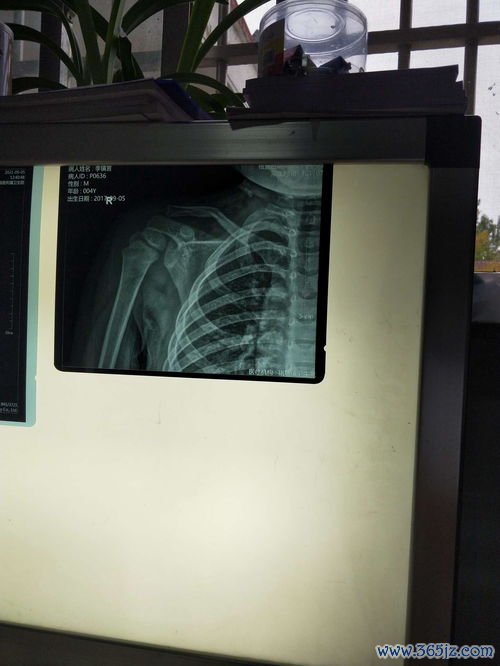

创伤:外伤

在人类纷繁复杂的生命经验中,“创伤”一词承载着多重意涵。它既指代心理上难以愈合的伤痕,也最直观地表现为身体的损伤——外伤。一道意外的伤口,一次骨折的剧痛,不仅是组织结构的破坏,更是生命与外界危险直接碰撞留下的物理印记。这类创伤超越年龄、性别与文化,是人类共有的脆弱性证明,同时也如同一面独特的镜子,映照出个体应对危机的能力、社会支持系统的效能,以及生命本身惊人...